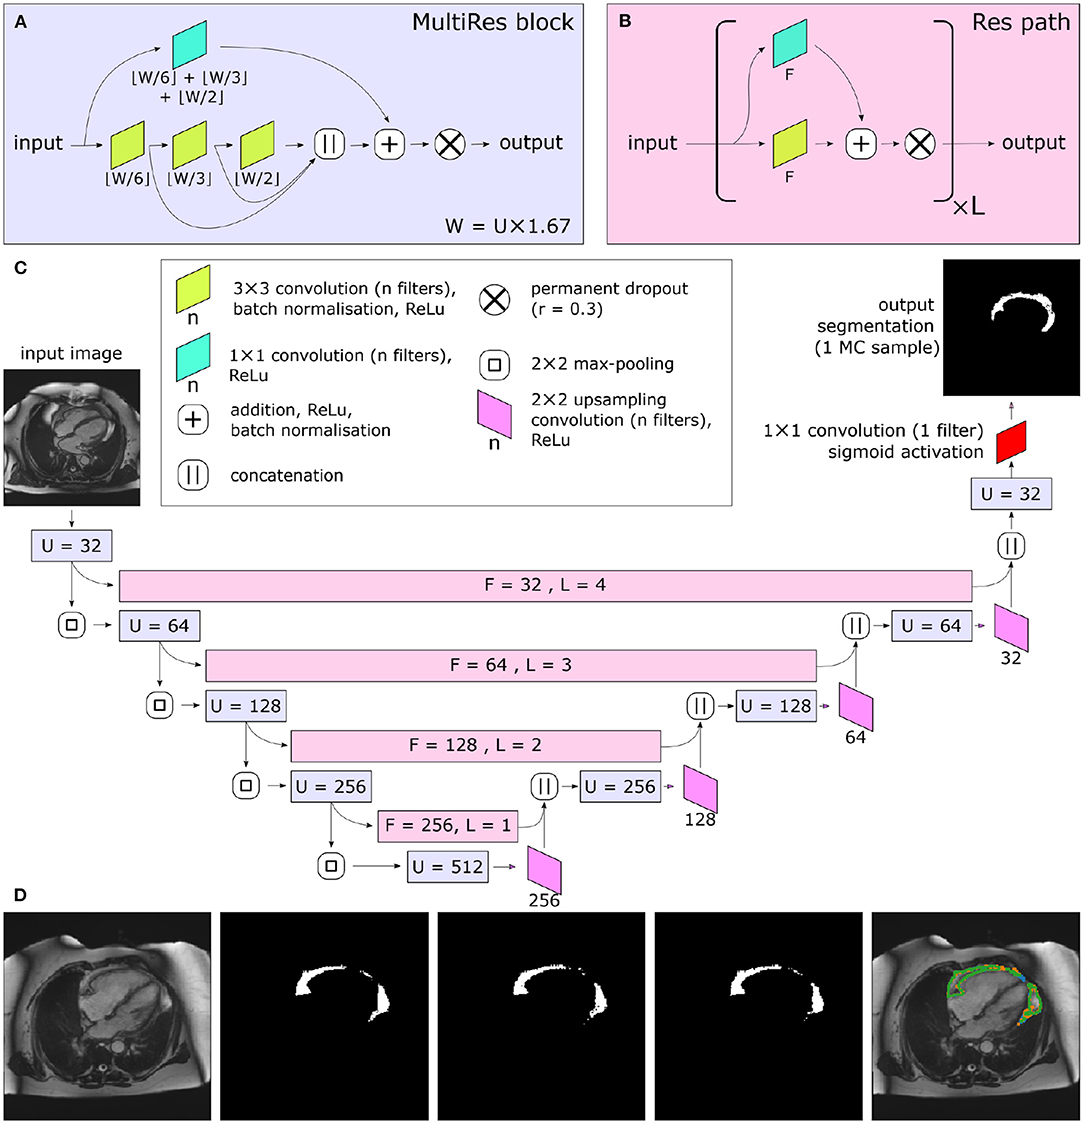

Great progress has been made with automated medical image segmentation using fully convolutional neural networks (20, 21), particularly using encoder–decoder architectures (22). We developed a neural network using a Multi-residual U-net (MultiResUNet) base architecture (23) with the incorporation of a permanently active dropout layer (24) at the end of each multi-residual block (Figure 2). The best trade-off between overall segmentation accuracy and prediction of that accuracy was obtained with a dropout rate r = 0.3, which we found to be optimal for model performance. This was selected as the largest r value at which the segmentation quality was not statistically reduced relative to a non-stochastic network (Supplementary Figure 1). To incorporate a measure of uncertainty that can be used for QC, we used permanently active dropout layers to add a stochastic component to their network outputs, meaning that multiple Monte Carlo (MC) samples can be drawn for any given input (24). This MC sampling from a stochastic neural network generates N samples of predicted probability maps {P1...PN}, from which thresholding at 0.5 can generate Boolean segmentation maps {S1...SN}. For our foreground detection problem, the final segmentation S for each voxel (x) is defined by thresholding the voxelwise mean of S:

Figure 2. Central illustration. Summary of model architecture used in the present study. The MultiRes blocks (A) form the encoder and decoder arms of the network. The number of filters used throughout the different components of the block is parameterized by U. The encoder and decoder arms are joined by Res paths (B), which are parameterized by F and L. They are formed of L repeating units, and their convolutional components each have F filters. The complete network is shown in (C). In (C), the colors indicate the placement of MultiRes blocks (A) and Res paths (B), while the hyperparameters used in each instance of the blocks are indicated as overlaid text. Because of the permanently active dropout components, each prediction the network makes is equivalent to a Monte Carlo (MC) sample. (D) shows three such samples drawn based on the same input image. Note the disagreement at the edges of the segmented regions, particularly clear as shown on the overlay (far right). Images reproduced with permission of UK Biobank.

We trained a MultiResUNet (23) with a Bayesian modification, such that multiple MC samples are drawn for each input, in order to perform QC and derive measures of uncertainty (24). Within this context, there is one hyperparameter that must be optimized after model training—that of the number (N) of MC samples drawn when segmenting an unseen image. When multiple MC samples are drawn during segmentation, they can be summarized in a number of ways. Firstly, they can be used to produce a single “best-guess” segmentation, via a simple voxel-wise voting procedure. It is expected that drawing more samples from a well-trained network will increase its accuracy, but with diminishing returns. Where the area of “foreground” pixels is particularly of interest (as in this use case, quantifying the area of PAT), we can report the mean and standard deviation of the areas across the N samples, which can be used for propagating uncertainty in downstream calculations. N was set to 15 for all further work, for the following reasons: Comparisons of segmentation accuracy with a deterministic neural network showed that consistent with prior work (24), there was no sacrifice in segmentation quality by using a stochastic network relative to a deterministic one when N was set to an appropriate level (Supplementary Figure 1A). Additionally, increasing N beyond 15 gave very little extra segmentation accuracy (Supplementary Figure 1A) or estimated standard deviation of area.

There are a number of different metrics that were proposed as correlates of final segmentation accuracy; however, it was concluded that, of these, both the most conceptually convenient and the most easily interpretable are those corresponding to often-used segmentation accuracy metrics—the Dice score and the IoU of the MC samples (24). We tested calculation of both IoU and Dice score globally or mean pairwise over the MC samples, finding that the best predictor of true segmentation accuracy was the mean pairwise Dice score between the MC samples, assessed on quantitative measures of agreement with the true Dice score of the test set (Supplementary Figure 2). Further details, as well as relevant equations, are detailed in the Supplementary Material.

Technical Implications

In terms of the technical details of our neural network, the Multi-Residual U-net architecture (23) was vital, yielding far better results than “vanilla” U-nets (21) (data not shown). Meanwhile, a QC method has been demonstrated using an extension of a stochastic network, which approximates Bayesian MC sampling (24). Consistent with prior work, we find that measures of similarity between MC samples are correlated with segmentation quality; intuitively, this corresponds to how “sure” the network is of the output. However, in contrast, we found that the mean pairwise Dice score dMC yielded best prediction, in contrast to the global intersection-over-union IoUG used in previous work, and that an additional linear correction was required.

A potential consideration is whether better segmentation accuracy could be obtained via the removal of the stochastic component, thereby providing a single prediction. This would be undesirable for a number of reasons. Firstly, it is important to have some estimate of segmentation quality, which can only be provided if the actual segmentation is derived from our stochastic process. Secondly, a comparison with a non-deterministic MultiresUNet is provided in Supplementary Figure 1, and the accuracy is comparable with our stochastic model. However, note that dropout was not used within training of this network for the following reason: The MultiResUNet architecture makes extensive use of batch normalization. Because of a phenomenon known as variance shift, the combination of batch normalization and dropout often produces reduced accuracy once the dropout is “turned off” (35). However, this problem does not apply to our results, as the dropout is kept permanently active.